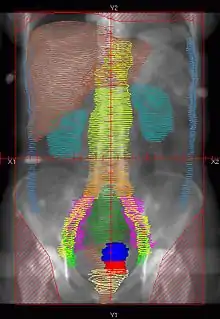

Example of a PA whole abdomen/pelvis radiation therapy treatment field used at Tufts/Brown residency program. Actual patient contours should guide field design.

• Superior border: Above the top of the diaphragm

• Inferior border: Inferior edge of pubic ramus

• Lateral borders: Lateral to peritoneal reflection

• Red: cervix; Blue: uterus; Khaki: bladder; Brown: rectum & liver; Teal: kidney; Light Blue: peritoneal reflection

• Orange: common illiac LNs; Yellow: external illiac LNs; Light Green: obturator LNs; Purple: internal illiac LNs; Dark Green: presacral LNs